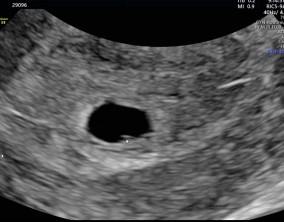

낮은 수치 속에서 피어난 기적

이유정 원장님만 믿고 따라가면 정말 든든하고 안심돼요. 치료 과정 내내 따뜻하게 응원해주시고, 설명도 명확해서 흔들림 없이 진행할 수 있었어요.